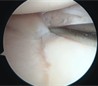

半月板は膝の内側と外側の両方に存在してクッションの役目を果たしており、外傷やスポーツなどによるオーバーユースにより損傷することがあります。また加齢による変性でも損傷します。手術では関節鏡を膝関節内に挿入して半月板の様子を確認してどのような手術を行うかを判断します。当院ではなるべく半月板を温存することを心掛けており、半月板縫合を行うことが多いですが、修復が難しい部位では部分切除が余儀なくされることもあります。

鏡視下膝半月板形成術

修復前